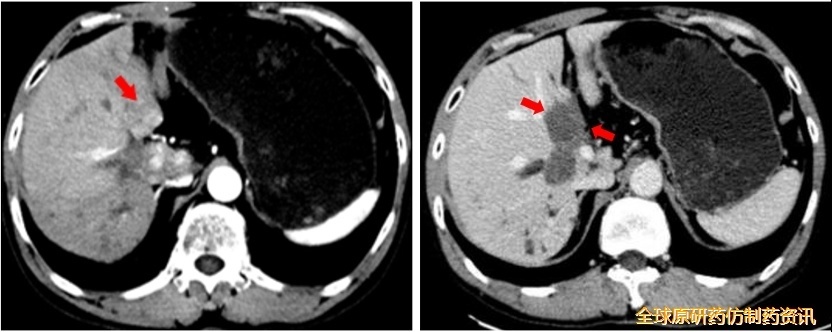

靶免联合方案治疗3个月后复查(2021.12)

AFP 8731 ng/mL;

MRI示肝S9c段下方稍低信号结节;

PET/CT提示S9c段结节氟代脱氧葡萄糖(FDG)代谢明显增高;考虑S9c段复发;全身其他部位糖代谢未见明显异常。

予以靶免联合方案+SBRT治疗(2022.01.06)

在“双艾”方案基础上对Ⅸc段复发病灶行SBRT治疗(共7次,累计剂量为56Gy);

放疗后,继续使用“双艾”方案治疗。

靶免联合方案+SBRT治疗后2个月后复查(2022.03)

AFP 2.91 ng/mL;

CT示肝Ⅸc段未见强化影,疗效评价为完全缓解(CR)。

图14 复发转移及治疗复查结果对比